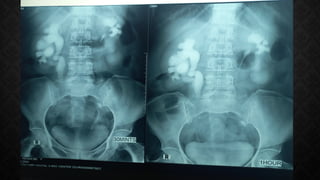

INTRAVENOUS

UROGRAPHY:

• Evaluation of

the function of

each kidney

• Identifying

any structural

abnormalities

• Assessing the

drainage of

urine